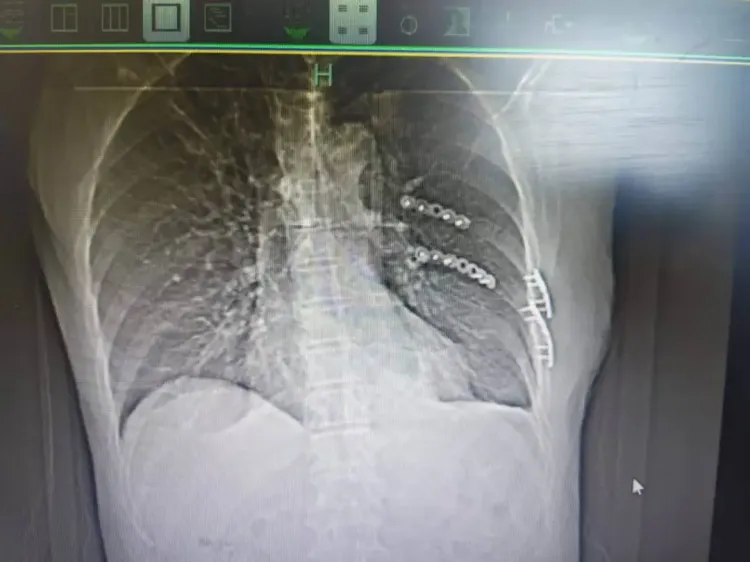

“患者被送到医院时,我们发现他共有13根骨头发生骨折,部分为单根多处断裂且合并左侧气胸。”接诊的杭州市富阳中医骨伤医院胸部创伤组莫军杰副主任医师对此感触很深,多发骨折会破坏胸廓稳定性,对中老年人而言更是“致命危机”:肋骨既是胸廓的保护支架,也是呼吸运动的助力器,一旦多根肋骨发生断裂,患者会本能地不敢深呼吸及咳嗽,这会导致肺部通气不足,痰液无法排出,进而引发肺部感染。

杭州市富阳中医骨伤医院供图